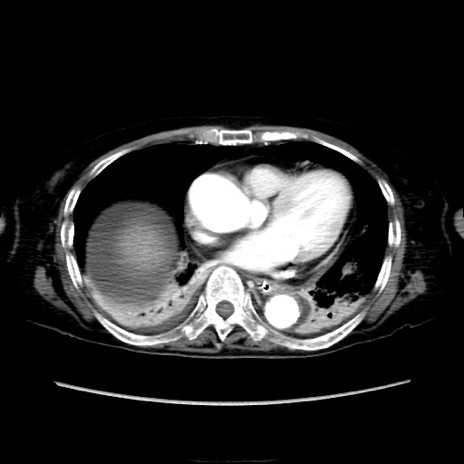

【症例】90歳代女性

【主訴】腹痛・嘔吐

【現病歴】 食欲低下、嘔吐があり昨日他院受診。肺炎と診断され入院となる。入院後より腹部全体に圧痛あり。胃管留置され経過みていたが、症状持続するため、

当院転院となる。

【既往歴】胸椎圧迫骨折、胆石症

【身体所見】腹部:中央に激痛あり、圧痛あり、反跳痛不明

【データ】WBC 17100、CRP 18.82

他院CT